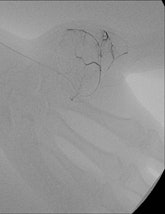

Nuclear medicine, with whom we work closely, has a PET/CT system that incorporates 64-detector-row CT, and has its own cyclotron. We also have two rooms for interventional radiology, and a new area is likely to open in summer 2013 in which vascular surgeons, cardiologists, and radiologists will work together in hybrid rooms. The idea is to have four new rooms, and we are really hoping this will go ahead.